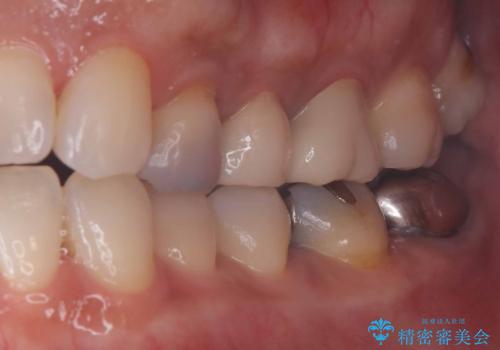

- 銀歯の下の虫歯です。お写真で分かるように広範囲で深い虫歯でした。

1歯はオールセラミッククラウンもう1歯はセラミックインレーで治療を行いました。

かなり虫歯が大きく深かったですが、神経は取らずに残す事が出来ました。